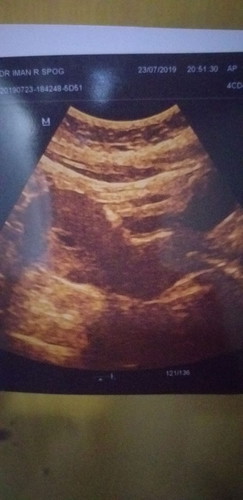

USG 5 Week

Ada yg pernah ngalamin gak bun? Sya hamil 5 week kemarin saya mengalami flek akhirnya saya periksa ke dokter lalu di USG, dan ternyata pas diusg kantung rahimnya gak normal katanya seharusnya yg normal itu bulat, nah punyaku ini lonjong bun, takutnya nanti janinnya gak bisa berkembang, tapi sama dokter masih diusahain dikasik obat penguat kandungan. lalu suruh kontrol lagi 1 minggu kemudian apakah janinnya berkembang atau tdk, klo tdk terpaksa hrus di kuret. Dan udah seminggu ini aku tetep keluar flek bun tapi dikit". Tolong berbagi pengalaman bund jika ada yg seperti saya.

Sabar aja dulu mom, masih 5w emang kantung ada yg kelihatan jelas ada yg enggak. Kadang juga ukuran 5w belum keliatan mom... Coba tunggu 2 minggu lagi mom. Kalo nggak ganti dokter dulu mom. Biar ada second opinion.